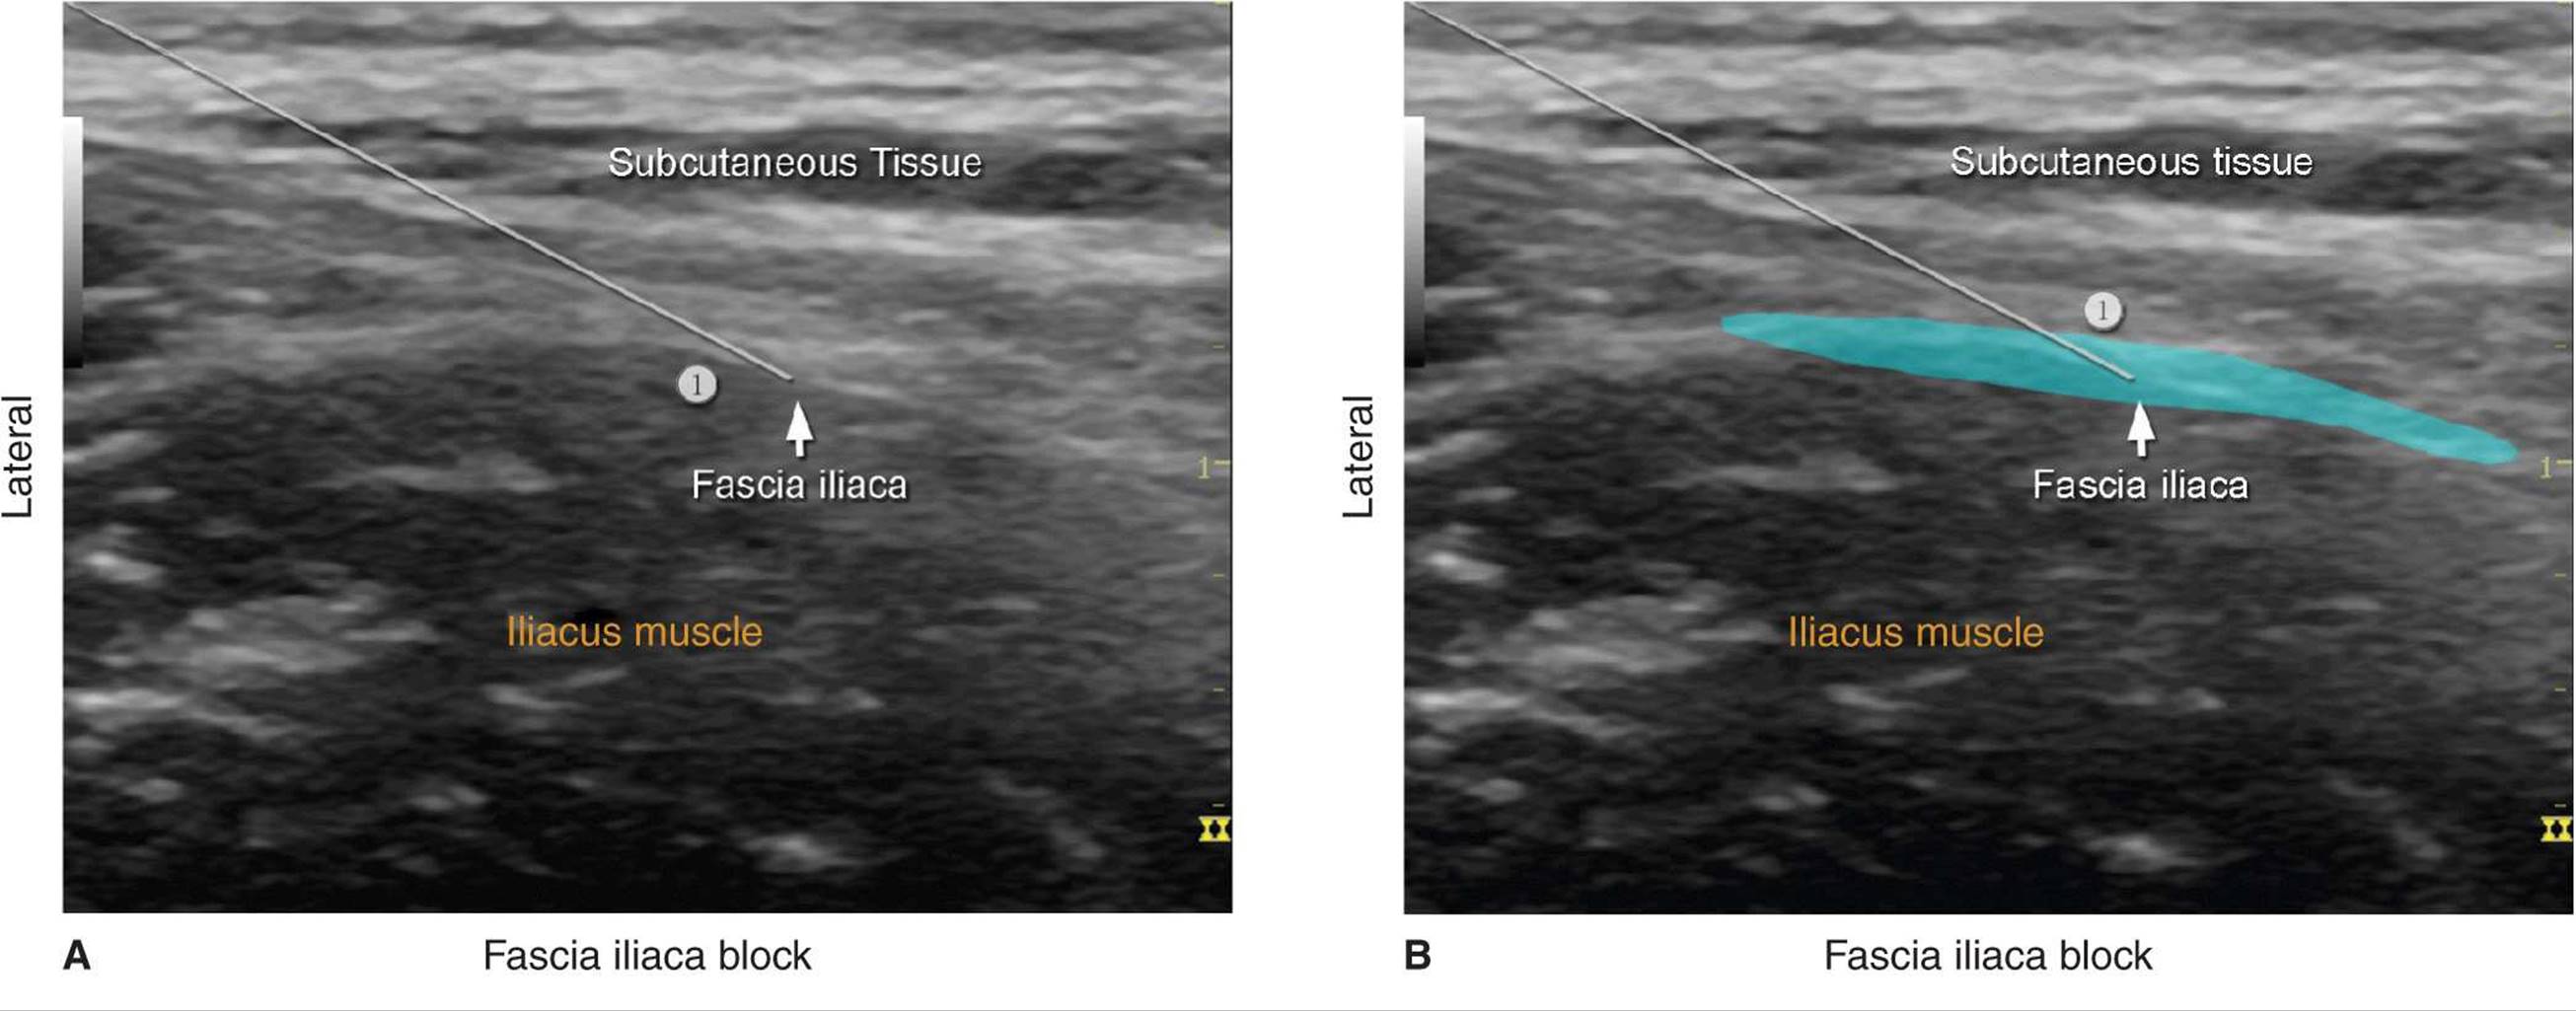

With the patient in the proper position, the skin is disinfected and the transducer positioned to identify the femoral artery and the iliopsoas muscle and fascia iliaca. The transducer is moved laterally until the sartorius muscle is identified. After a skin wheal is made, the needle is inserted in-plane (Figure 36-1). As the needle passes through fascia iliaca the fascia is first seen indented by the needle. As the needle eventually pierces through the fascia, pop may be felt and the fascia may be seen to “snap” back on the ultrasound image. After negative aspiration, 1 to 2 mL of local anesthetic is injected to confirm the proper injection plane between the fascia (Figure 36-4) and the iliopsoas muscle (Figure 36-5A, B, and C). If local anesthetic spread occurs above the fascia or within the substance of the muscle itself, additional needle repositions and injections may be necessary. A proper injection will result in the separation of the fascia iliaca by the local anesthetic in the medial-lateral direction from the point of injection as described. If the spread is deemed inadequate, additional injections laterally or medially to the original needle insertion or injection can be made to facilitate the medial-lateral spread.

FIGURE 36-5. (A) Path of the needle for the fascia iliaca block. The needle

is shown underneath the fascia iliaca lateral to the femoral artery (not seen) but not too deep to be lodged into the iliac muscle. (B) A simulated spread (area shaded in blue) of the local anesthetic to accomplish a fascia iliaca block. (C) Spread of the local anesthetic (LA) under the fascia iliaca. Some local anesthetic is also seen deep within the iliacus muscle (yellow arrows). When this occurs, the needle should be pulled back more superficially. (D) Extension of the LA laterally underneath the sartorius muscle. Some LA fills the adipose tissue between fascia iliaca and iliacus muscle (yellow arrows).